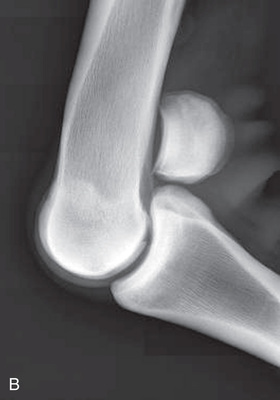

| Elbow joint | Cranioproximal-caudodistal (CrPr-CdDi)—standing | Craniocaudal (CrCd) |

| Mediolateral standing (ML) | Lateral (L) | |

| Optional views | Cranioproximal-craniodistal oblique (CrPr-CrDiO) of olecranon | Skyline or flexor |

| Lateromedial (LM) | Lateral (L) | |

The elbow joint is difficult to radiograph while the animal is in a standing position because of its proximity to the ventral body wall. The use of general anesthesia is preferred if possible. Because of the increased thickness of the limb, higher-capacity x-ray equipment is required.

With the patient standing, the mediolateral view is the easiest positioning for the elbow and is often suitable for a portable x-ray unit.

| Elbow joint | CdCr (Standard) | Caudoproximal-craniodistal- standing (CdPr-CrDi) | Weight-bearing with limbs evenly on ground and cassette against cranial aspect of joint at angle to the x-ray beam. | Caudal to joint; parallel to ground so beam perpendicular to radius. |

| Lateral (Standard) | Lateromedial standing (LM) | Weight-bearing with limbs evenly on ground; cassette against medial aspect of joint at angle to the x-ray beam. | 90 degrees lateral to MSP, parallel to ground on either the elbow joint or olecranon if required. | |